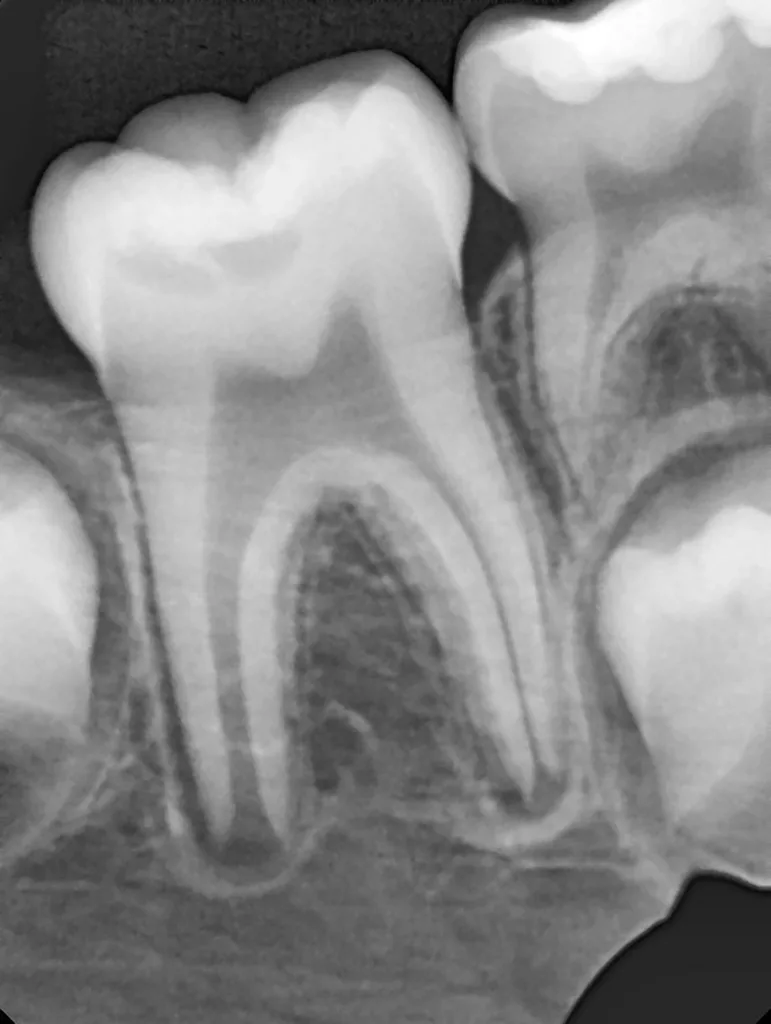

Bei routinemäßigen Röntgenkontrollen ergeben sich manchmal Zufallsbefunde unklarer Genese. So stellt sich beispielsweise bei der Betrachtung der Abbildung 1 die Frage, wie sich ein Zahnhartsubstanzdefekt so schnell entwickeln konnte. Ein weiteres Röntgenbild (Abb. 2), das vor dem Zahndurchbruch aufgenommen wurde, zeigt jedoch, dass es sich in diesem Fall nicht um Karies, sondern um die sogenannte präeruptive intrakoronale Resorption (PEIR) handelt. Für diesen Befund finden sich in der Fachliteratur auch noch andere Bezeichnungen wie „idiopathic external resorption of unerupted permanent teeth“ [1], „intra-follicular caries“ [2], „radiolucent lesions resembling caries“ [3], „occult caries“ [ 4] oder „pre-eruptive caries“ [5].

V. Slabkovskyi, O. Liutikovwährend des Durchbruchs des Zahnes 36.

Das fünfjährige Mädchen stellte sich 2017 zur jährlichen Routinekontrolle vor. Im Rahmen der Untersuchung wurden Röntgenaufnahmen der Milchmolaren gemacht (Abb. 2). Der klinische und radiologische Befund der vor uns früher gelegten Kompositfüllungen war gut, es wurde allerdings eine PEIR an den noch nicht durchgebrochenen ersten bleibenden Molaren festgestellt (Abb. 2). Den Eltern wurde empfohlen, sich unverzüglich bei Beginn des Durchbruchs der ersten Molaren erneut zur Behandlung vorzustellen. Ein Jahr später erschien die junge Patientin schmerzfrei zur Kontrolle. Der Zahn 36 war noch teilweise mit Gingiva bedeckt. Auf einer neuen Röntgenaufnahme (Abb. 1) wurde die PEIR-Läsion mit unveränderter Größe in pulpanahen Bereichen bestätigt (Grad 3 der Läsion nach Seow). Der Zahnschmelz sah intakt aus, es konnte kein pathologischer periapikaler Befund bei den noch nicht ausgewachsenen Zahnwurzeln festgestellt werden. Daraufhin wurden die verschiedenen Behandlungsmöglichkeiten von Fissurenversiegelung bis Vitalerhaltung der Zahnpulpa mit den Eltern des Kindes besprochen.